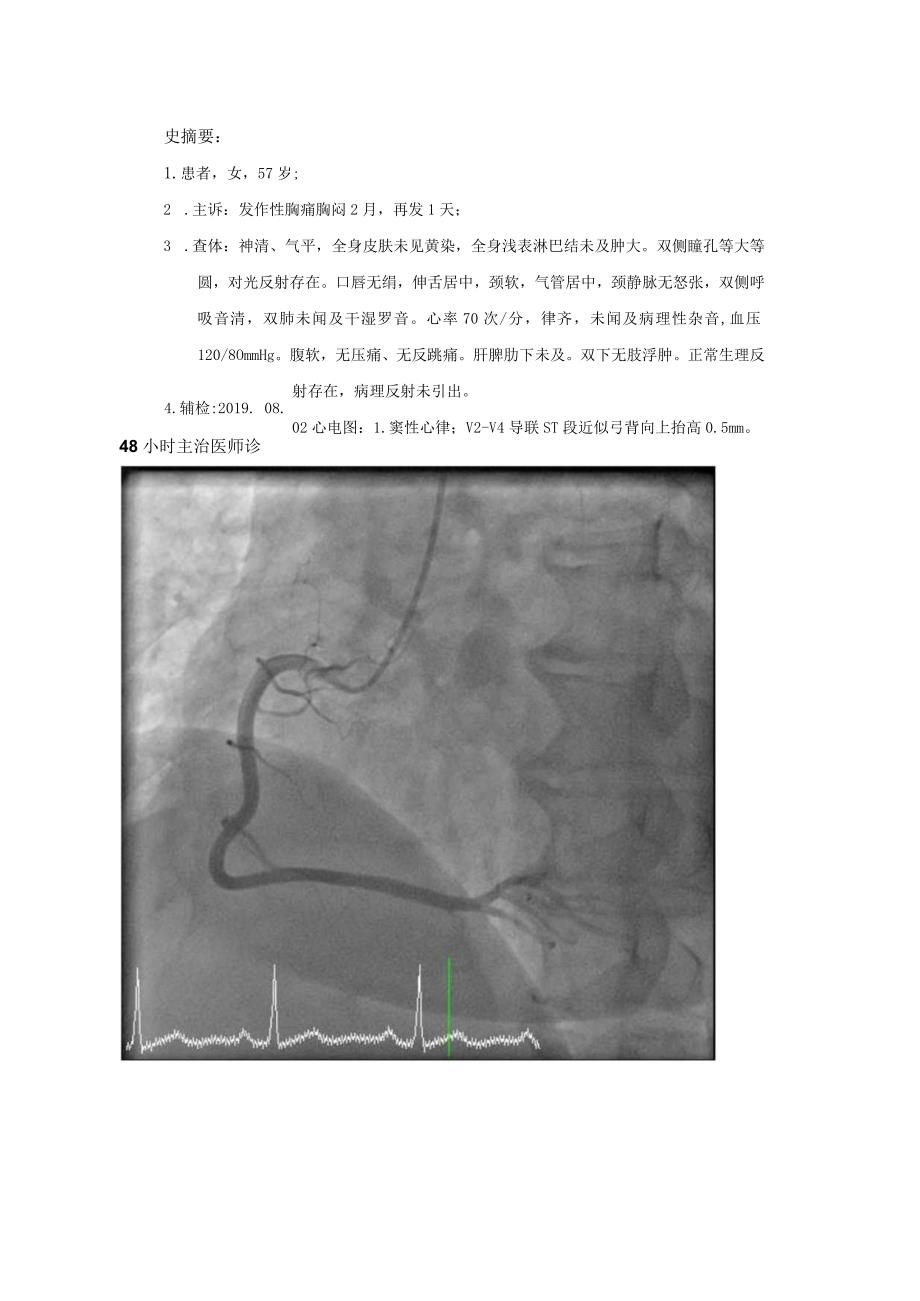

4.辅检:2019. 08.48小时主治医师诊断:史摘要:1.患者,女,57岁;2 .主诉:发作性胸痛胸闷2月,再发1天;3 .查体:神清、气平,全身皮肤未见黄染,全身浅表淋巴结未及肿大。双侧瞳孔等大等圆,对光反射存在。口唇无绢,伸舌居中,颈软,气管居中,颈静脉无怒张,双侧呼吸音清,双肺未闻及干湿罗音。心率70次/分,律齐,未闻及病理性杂音,血压120/8OmmHg。腹软,无压痛、无反跳痛。肝脾肋下未及。双下无肢浮肿。正常生理反射存在,病理反射未引出。02心电图:1.窦性心律;V2-V4导联ST段近似弓背向上抬高0.5mm。不稳定性心绞痛冠心病高血压3级(很高危)WAV郴郴郴郴M产2如郴郴郴l崛八郴蜘郴脾柚腑榔抑曲岫V